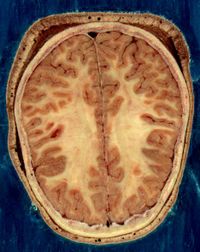

Horizontal bisection of the head of an adult man, showing skin, skull, and brain with grey matter (brown in this image) and underlying white matter

ويسمى أيضًا الليف العصبي، ويشكل امتدادًا أنبوبيًا للجسم الخلوي للعصبون. وله العديد من التفرعات التي تمكنه من الاتصال بما يقرب من ألف عصبون آخر. وهو متخصص في نقل الرسائل. يبلغ طول المحوار داخل الجهاز العصبي المركزي أقل من مليمتر واحد، بـينما يزيد عن ذلك في الجهاز العصبي المحيطي، إذ يصل طول بعض المحاوير الممتدة من النُخاع الشوكي إلى عضلات القدمين إلى 75-100سم. أما الأعصاب فما هي إلا تجمعات لمحاوير عصبونات حركية أو حسية أو لكليهما معًا، التصقت مع بعضها مع بعض مكونة ذلك الشكل الحبلي. يغطي غمد مصنوع من مادة دهنية بيضاء تسمى الميلين بعض المحاوير، حيث تساعد على سرعة انتقال الدفعات العصبية عبرها، كما تساعد على التمييز بين المادة الرمادية والمادة البيضاء في الجهاز العصبي. وتتكون المادة الرمادية من محاوير غير مغطاة بالميلين وأجسام خلوية عصبونية، بينما تتكون المادة البيضاء من محاوير مغطاة بالميلين. وتصنع مادة الميلين في خلايا شفان في الجهاز العصبي المحيطي، بينما تقوم الخلايا الدبقية بتصنيعها في الجهاز العصبي المركزي.